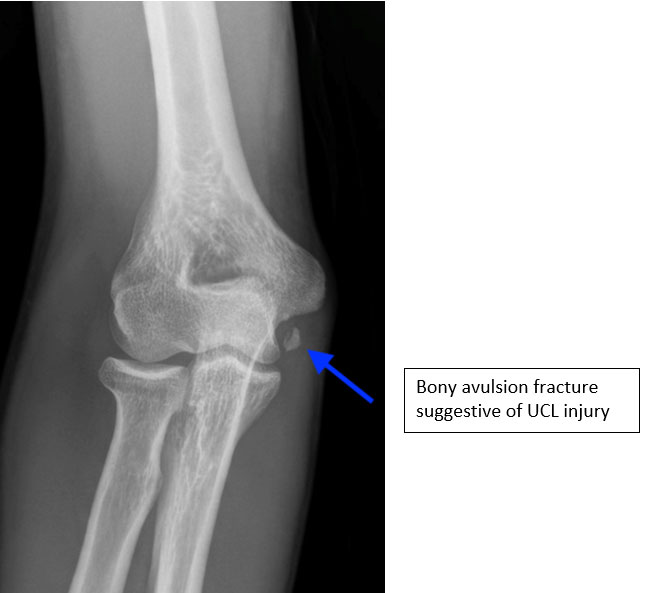

- An athlete with a suspected UCL injury will undergo initial X-rays to look for any loose bodies, stress fractures, bone spurs or even avulsion fractures

Proximal Ulnar Collateral Ligament reconstruction with chronic calcified ligamentous changes and bony fragments not amenable to repair and therefore requiring reconstruction